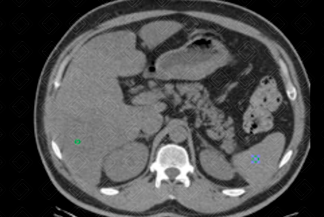

Texto alternativo para a imagem Figuras 1 e 2. Créditos: Dra. Elazir Mota - Rio de Janeiro/RJ

Descrição da lesão: Tomografia computadorizada do abdome, em fase sem contraste venoso. Foram medidos os coeficientes de atenuação hepáticos e esplênicos, com uma diferença entre eles superior a 10 UH, compatível com esteatose hepática (densidade hepática de 28 UH e esplênica de 42 UH).